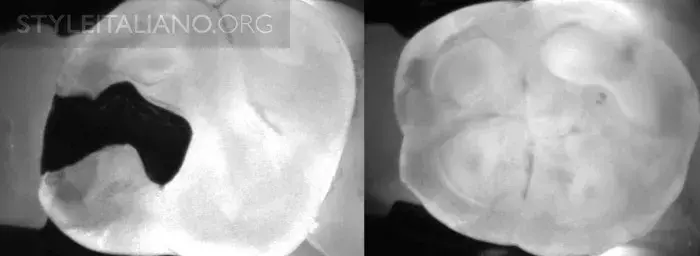

Рис. 3 Устройство Diagnocam, в основе которого лазерно-индуцированное просвечивание, позволяет нам просветить жевательные поверхности зубов. Выражается в серой шкале. Различные ткани зуба реагируют на свет по-разному: эмаль светлая, дентин более серый, а полости гораздо темнее.

DiFOTI (Digital Fiber Optic Trans Illumination) – здесь используется инфракрасное свечение.

Рис. 4 – Эта технология позволяет найти кариес на ранней стадии. Ткани серого цвета нуждаются в мониторинге.